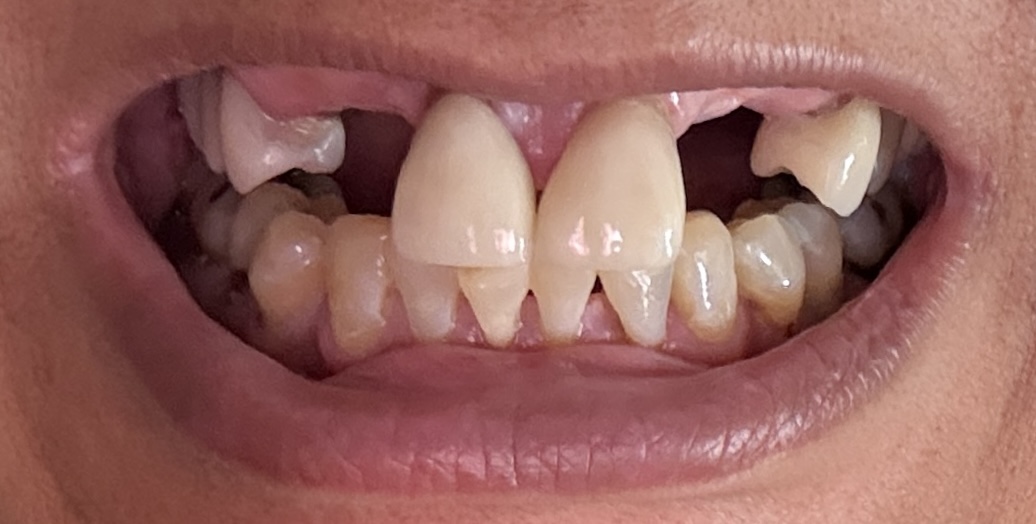

Dental Auction No. 11561: Several extractions and All-on-4 Top and bottom arches

12,13,14 have had root canals in past and now have quite a bit movement. 2-5 have all had root canals in past and now the crowns are breaking down.

Overall, all of my gums have receded and most of the bottom teeth are exposed w/ some roots and there are many cavities.